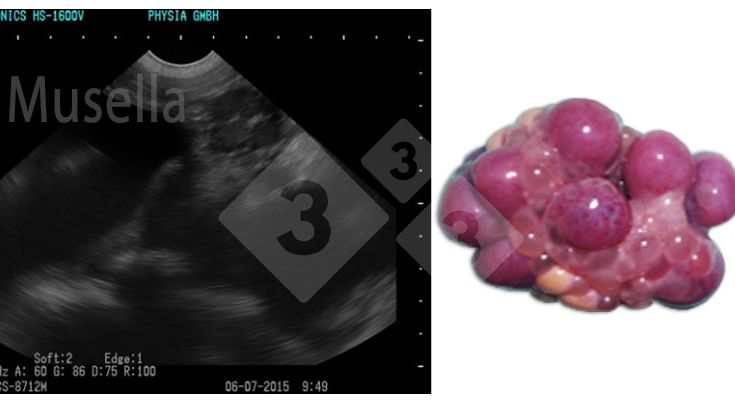

A ecografia pode ser usada para visualizar as estruturas ováricas, avaliar o estado puberal e diagnosticar patologias ováricas.